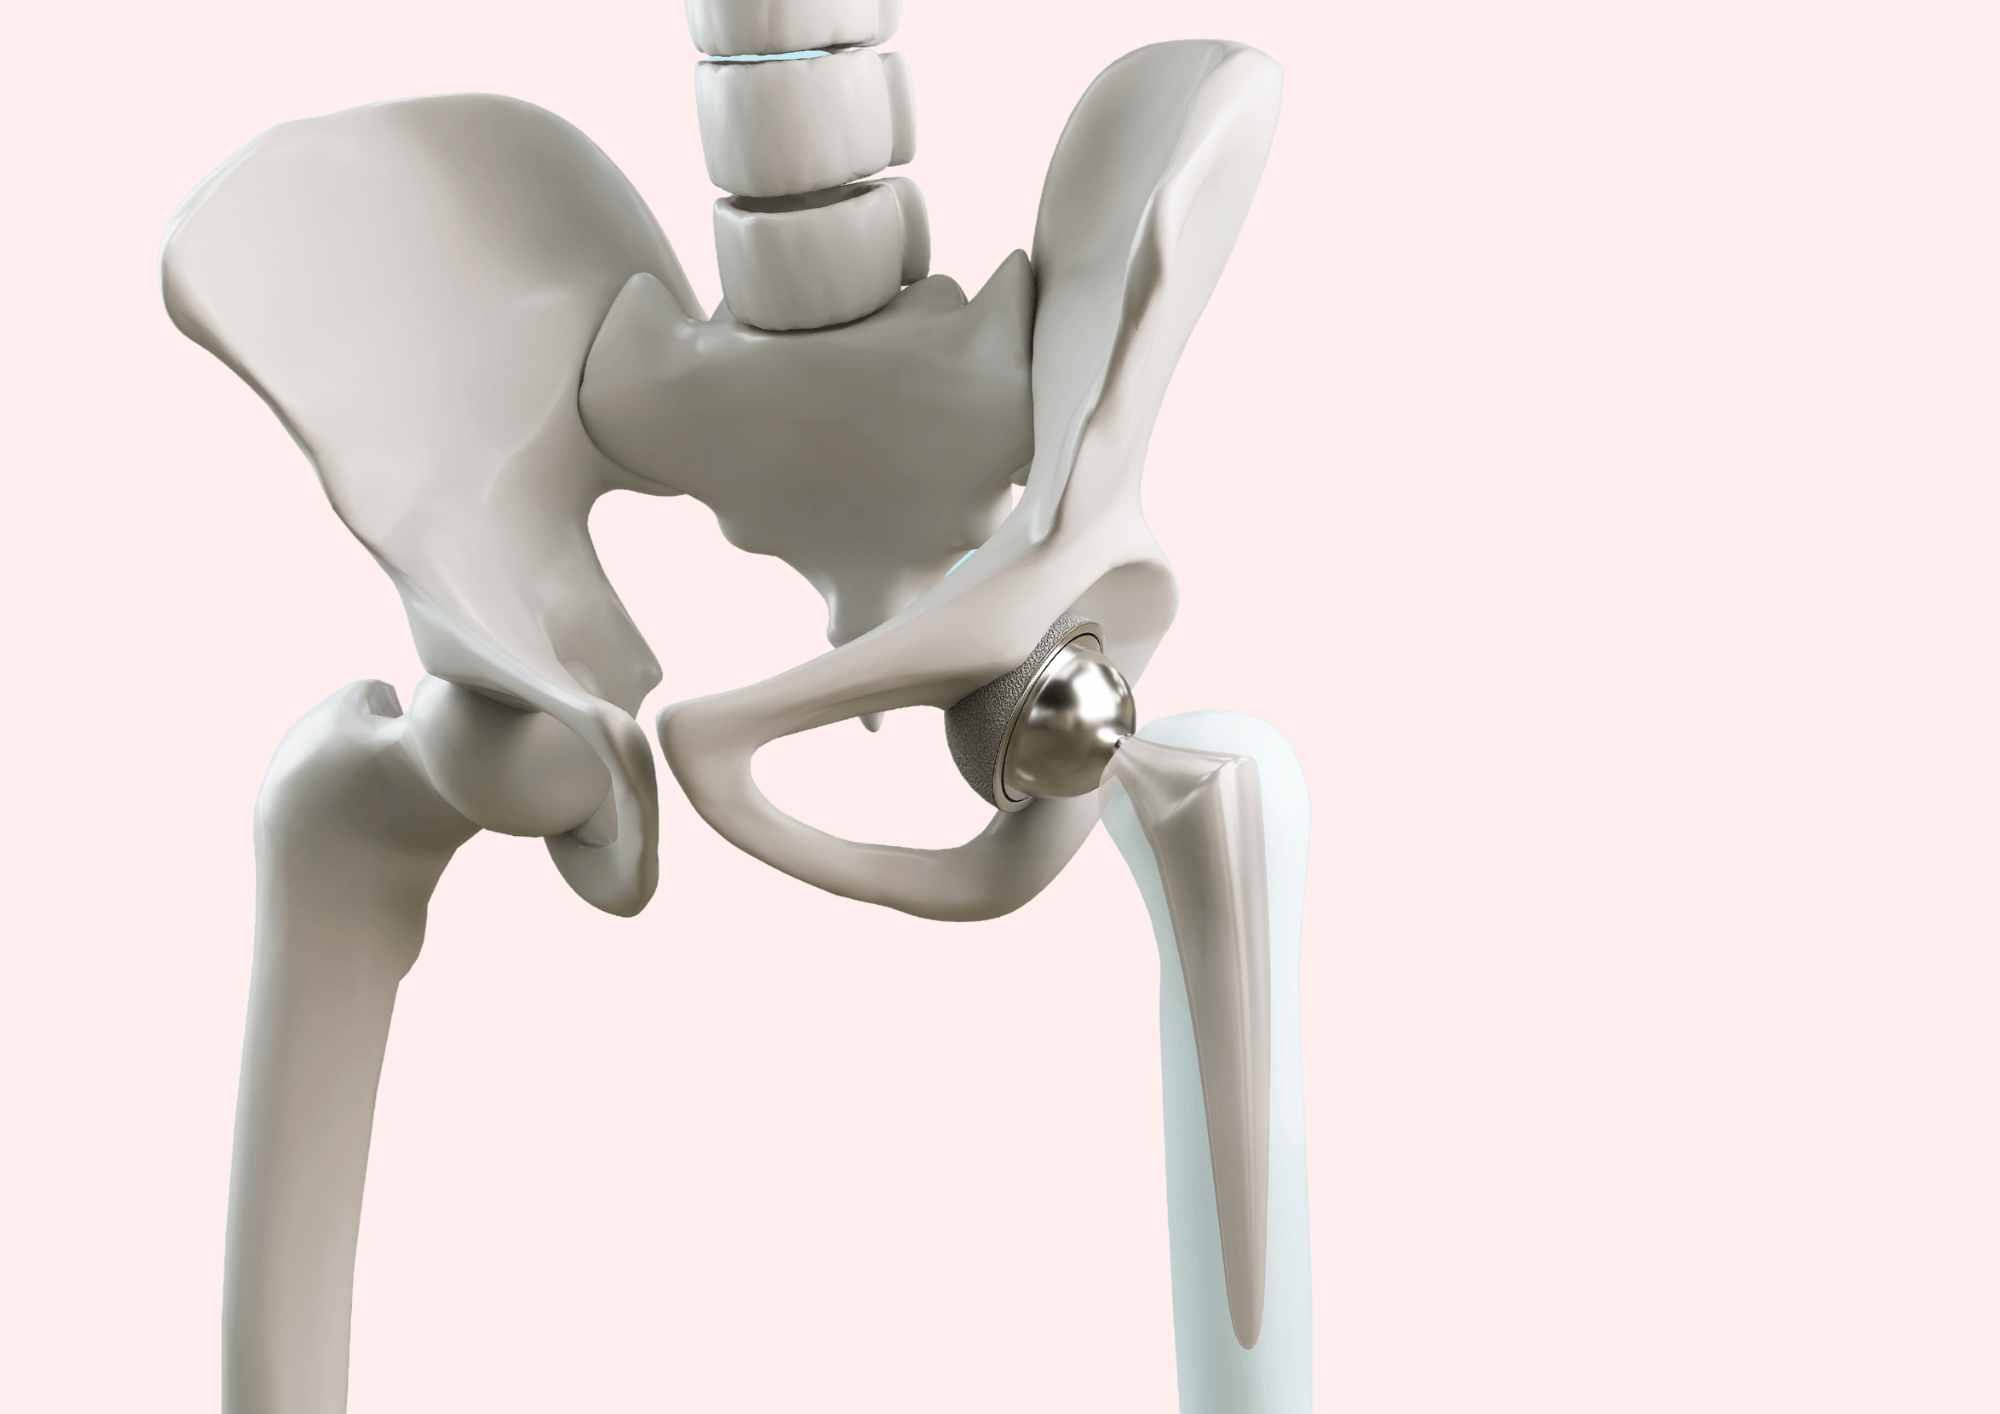

Замена таз сустава

Замена таз сустава 113 фотографий